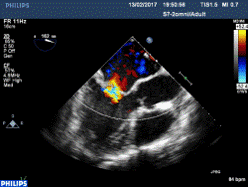

Avaliação Ecocardiográfica de Insuficiência Mitral

Avaliação Ecocardiográfica de Insuficiência Mitral Severa